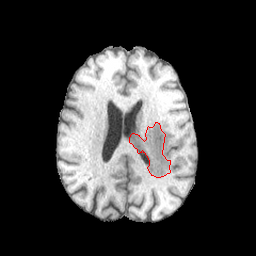

Refer to caption

(a)

(b)

(c)

(d)

(e)

(f)

(g)

(h)

Figure 2: Samples patches from BCSS (a-d) and BraTS 2020 (e-h) with their respective tumor ground truths marked in red.

As the focus of this work is on possible applications of SAM in the medical domains, we evaluate on the radiology dataset BraTS and the pathology dataset BCSS. Figure 2 shows sample patches from both datasets. The following sections provide more details on each dataset.